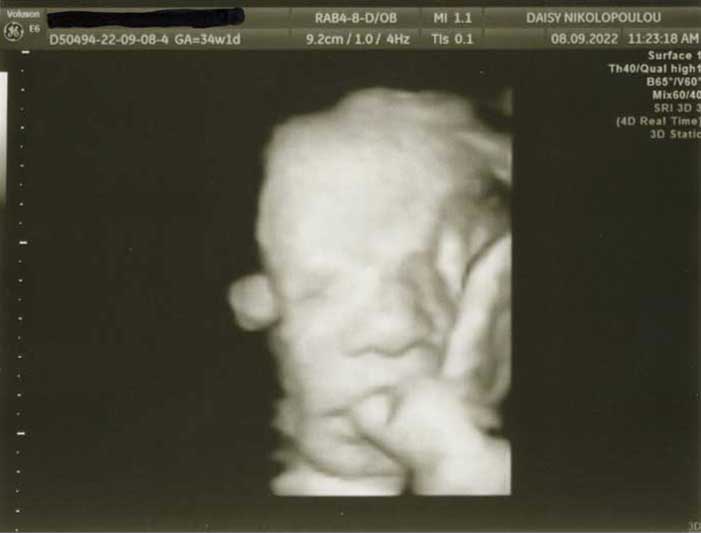

3D/4D HD LIVE

Στο ιατρείο μας προσφέρουμε υψηλής ευκρίνειας 3D και 4D τεχνολογία απεικόνισης του εμβρύου. Η τεχνολογία αυτή αποτελεί ένα ακόμα σημαντικό διαγνωστικό όπλο στη φαρέτρα του προγεννητικού ελέγχου, ενώ ταυτόχρονα ενισχύει την ανάπτυξη του δεσμού ανάμεσα στους μελλοντικούς γονείς και το μωρό τους.